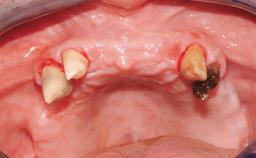

Conventional Loading of Eight Implants in the Maxilla and Final Restoration with a Full-Arch Gold-Ceramic FDP

A 35-year-old Caucasian female presenting with advanced periodontal disease involving both the maxillary and the mandibular dentition was referred for evaluation. The patient, a non-smoker in good general health, requested treatment for recurrent periodontal abscesses, tooth mobility, and discomfort during chewing, as well as restoration of her missing teeth with a fixed prosthesis to improve mastication and esthetics. All residual maxillary teeth exhibited plaque deposits, deep pockets, bleeding on probing, and class III mobility and were evaluated as hopeless. All residual mandibular teeth except tooth 37 could be maintained after periodontal therapy.

Case Type Edentulous Maxilla

Jaw Maxilla